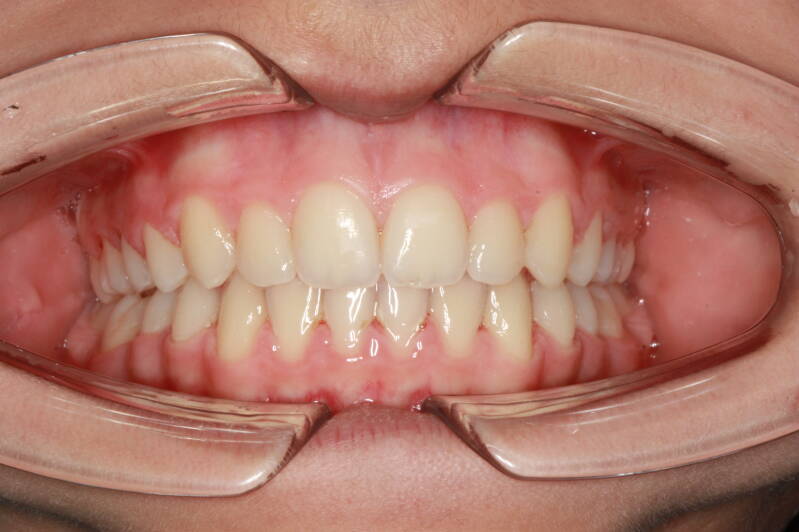

FOTO FINALI DOPO 24 MESI CIRCA DI TERAPA ORTODONTICA FISSA

Abbiamo appena portato a termine questo caso che presentava in arcata superiore il primo premolare di sinistra completamente fuori arcata sovrapposto al secondo premolare ed il canino ruotato.

in arcata inferiore invece abbiamo estratto il secondo molare di sinistra perso per carie deostruente e mesializzato il terzo molare in modo da chiudere lo spazio e non ricorrere all'inserimento di protesi implantare.